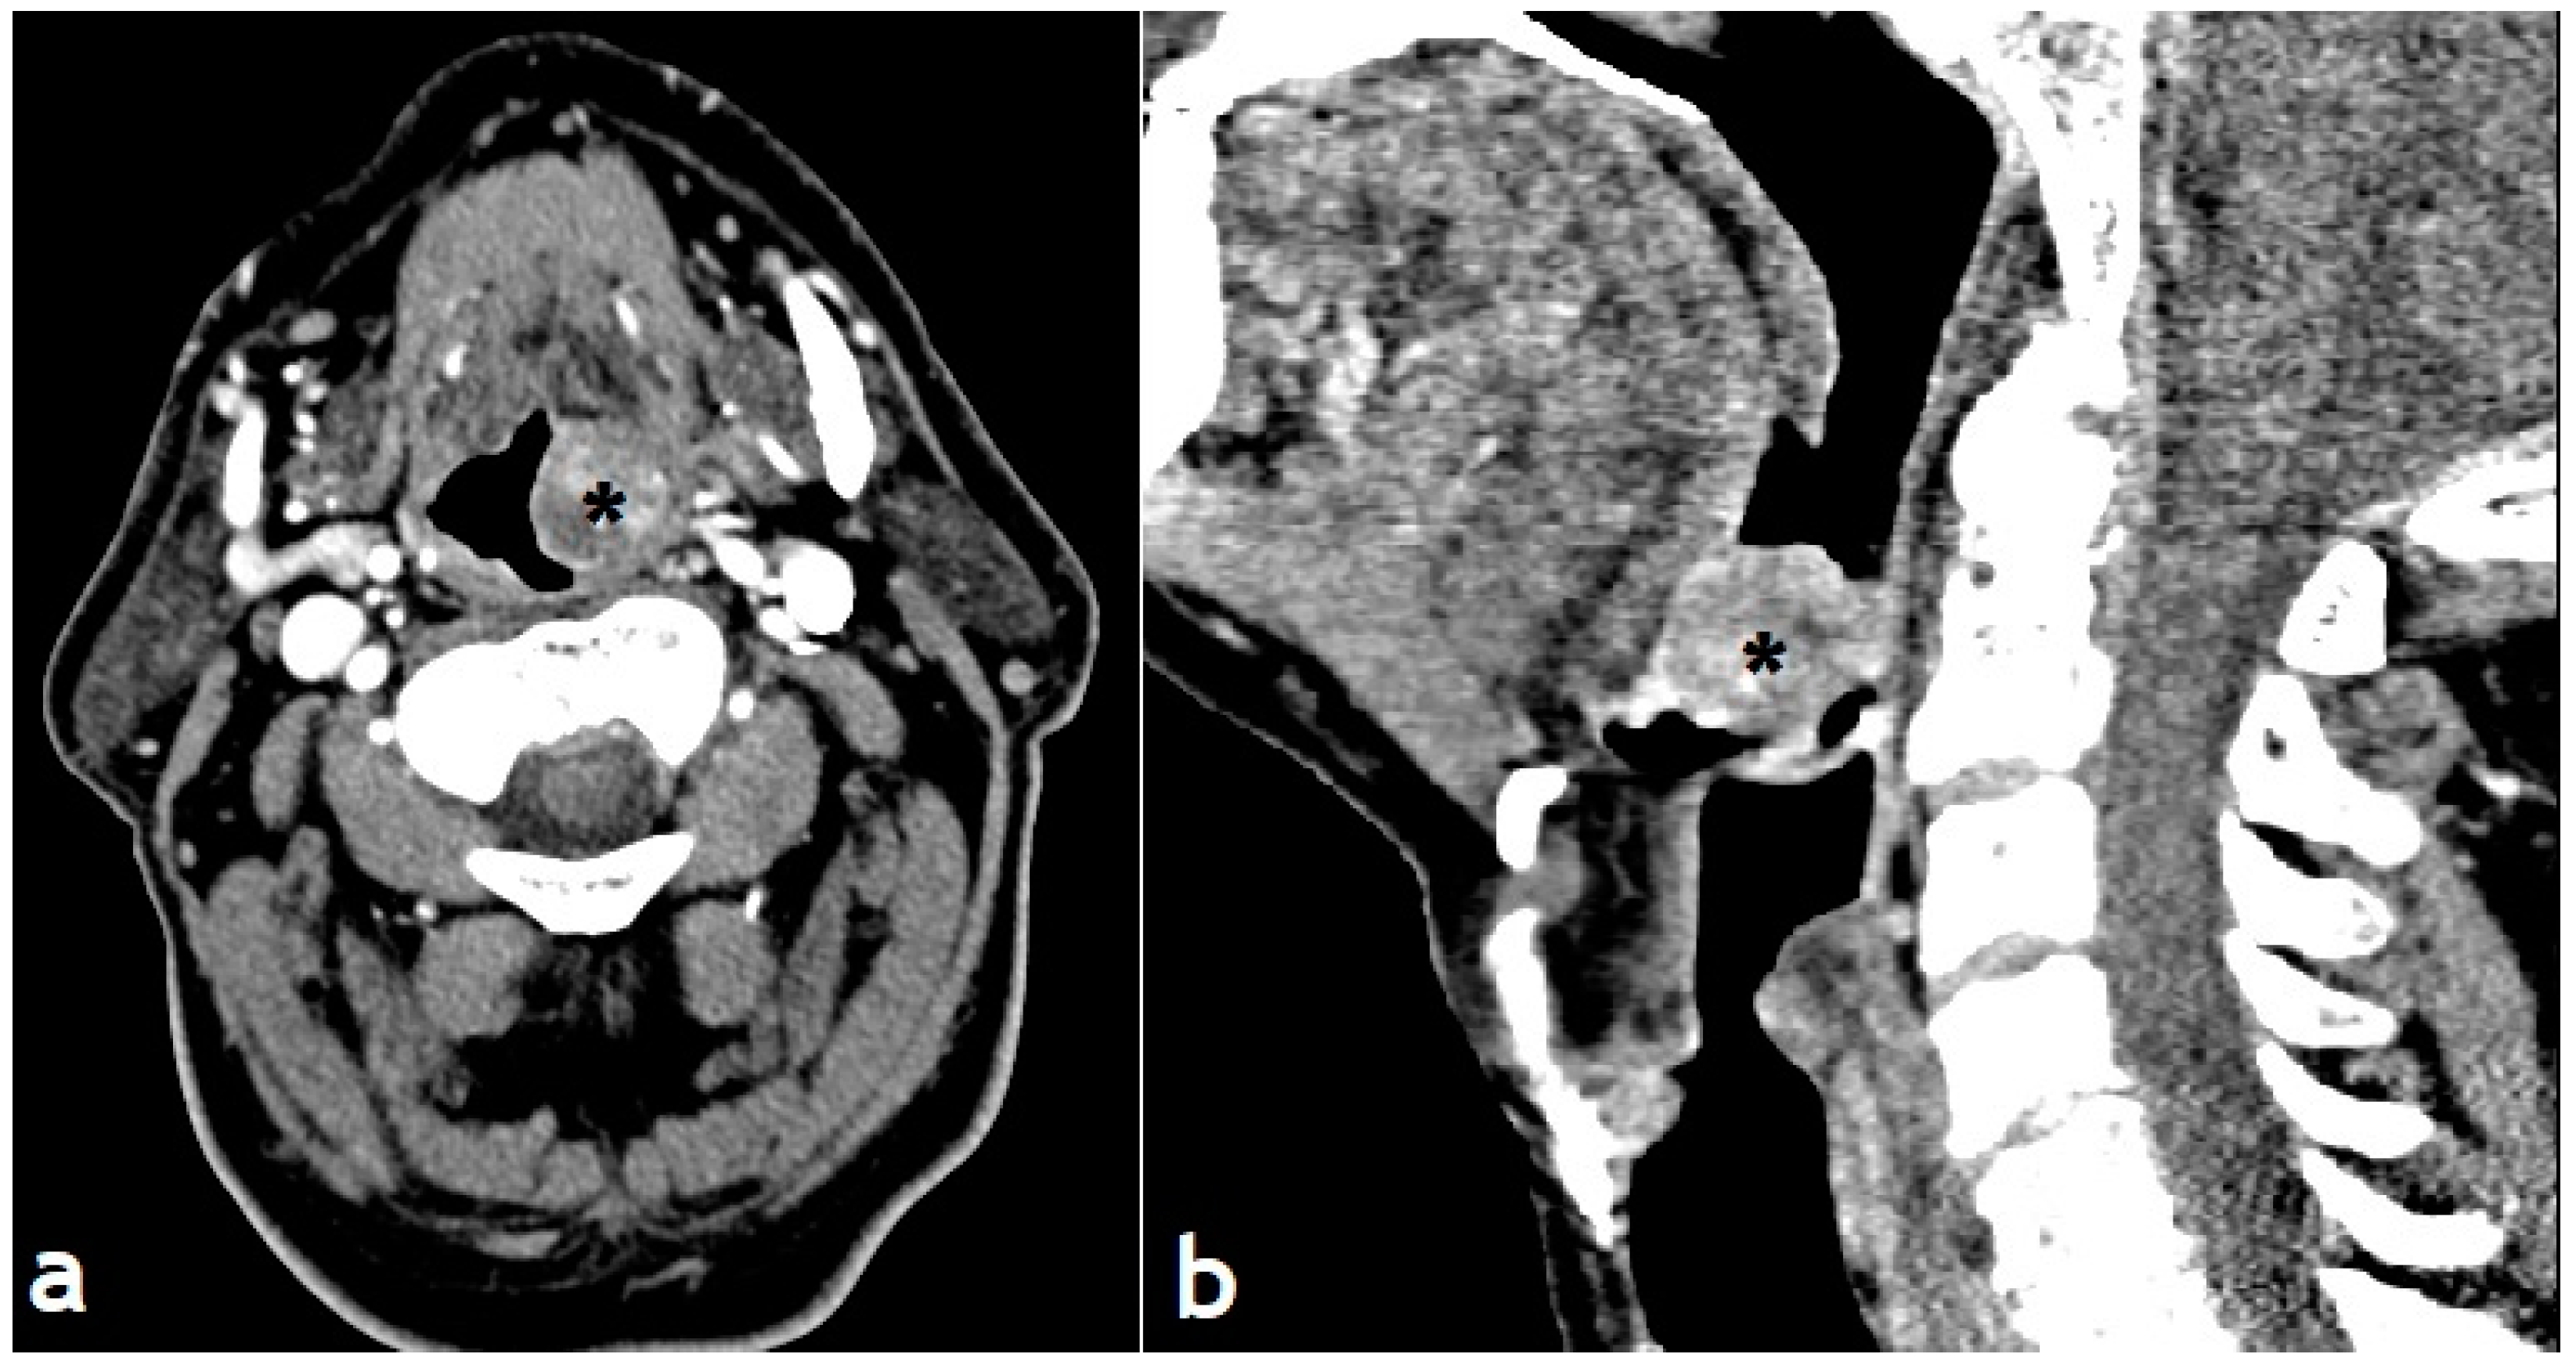

Computed tomography (CT) revealed a 2.0-cm-sized well-circumscribed inhomogeneous left tongue base mass with no evidence of involvement or destruction of adjacent structures. These findings indicated a tumor with potentially rich vascularisation (Figure 2).

Figure 2. Preoperative CT scan showing a 2 cm well-defined mass originating from the left tonsillar pillar and extends to the supraglottic plane causing deviation of the oropharyngeal lumen.